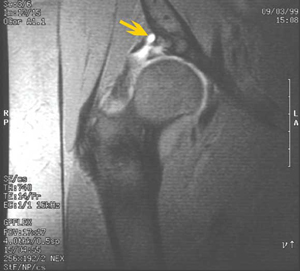

1 Tear of the acetabular labrum

T2 fat-saturated magnetic resonance image showing labral tear (lower white area) and paralabral cyst (arrow).